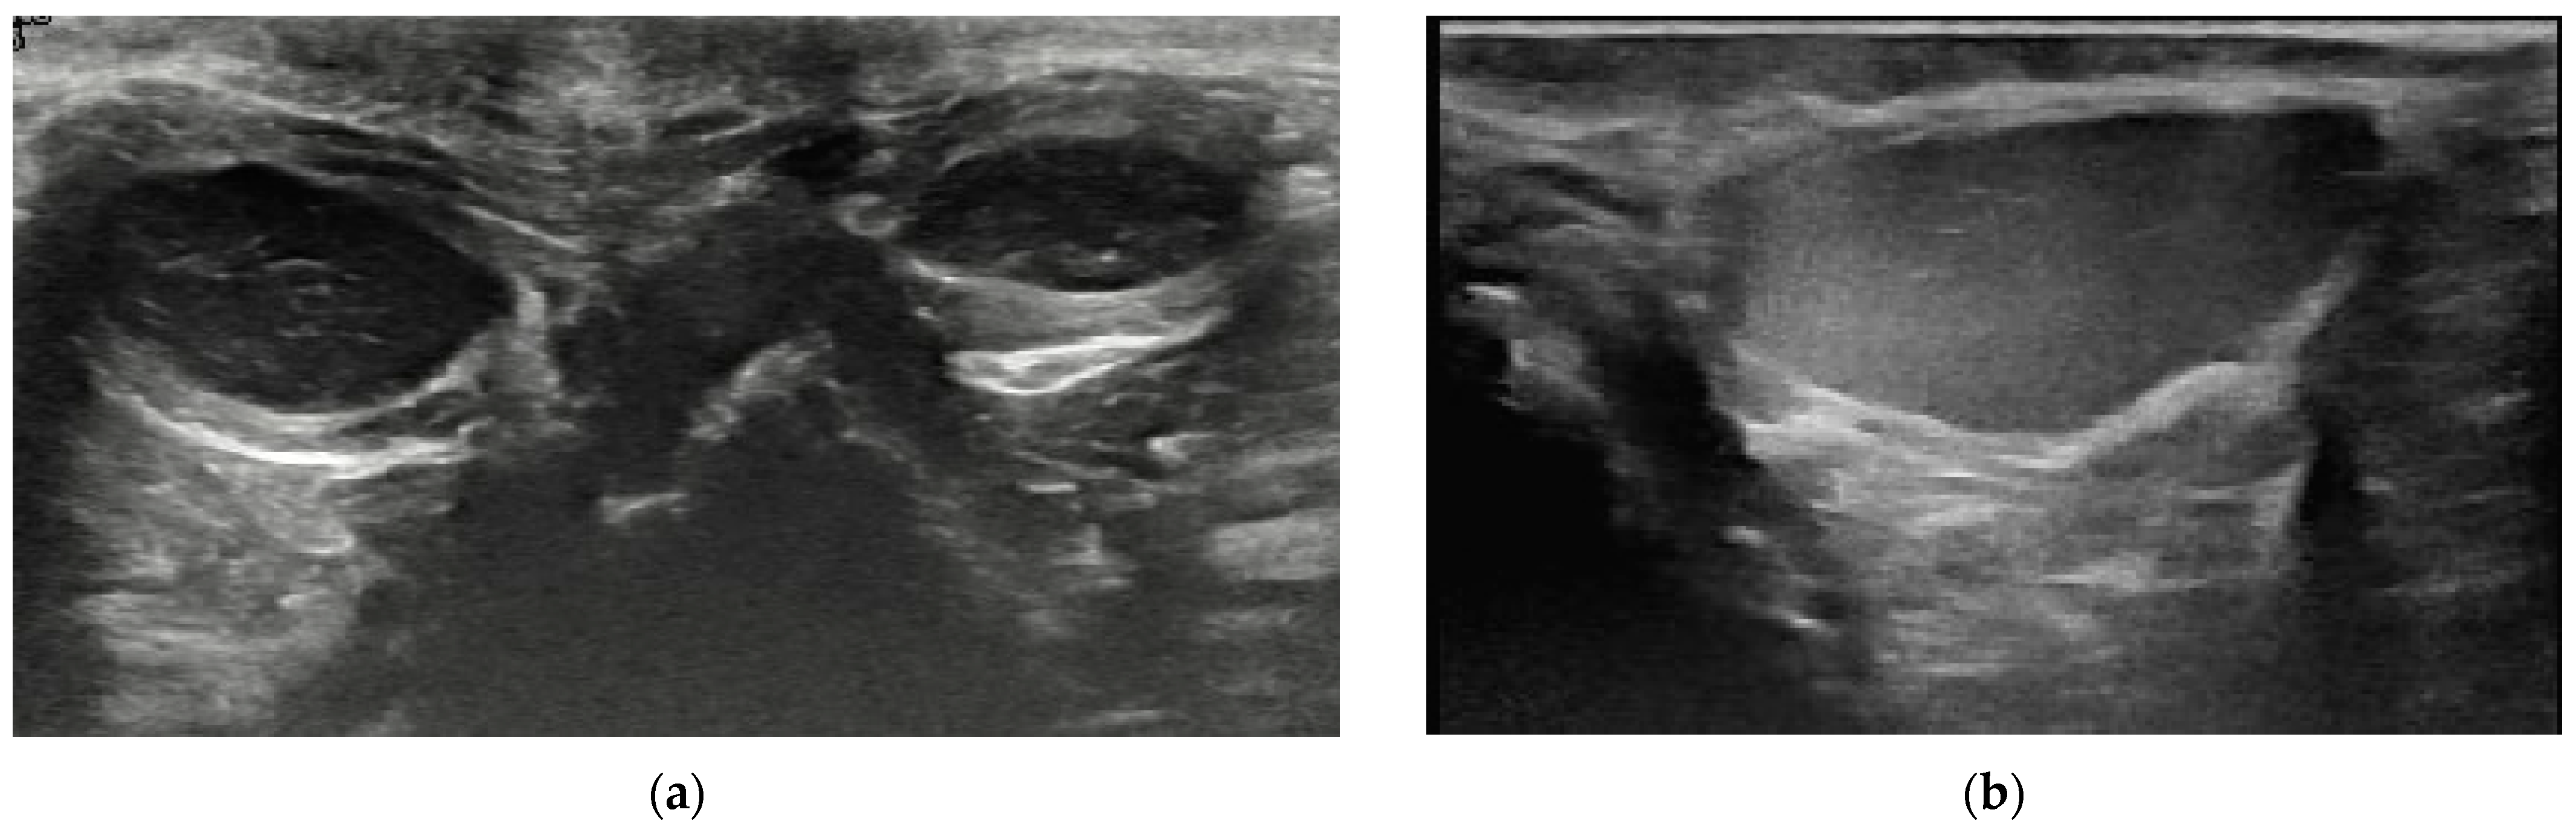

3.2. Content of Anal Sacs

3.3. Size and Shape of Anal Sacs

3.4. Wall of Anal Sacs

3.5. Adverse Findings

4. Discussion